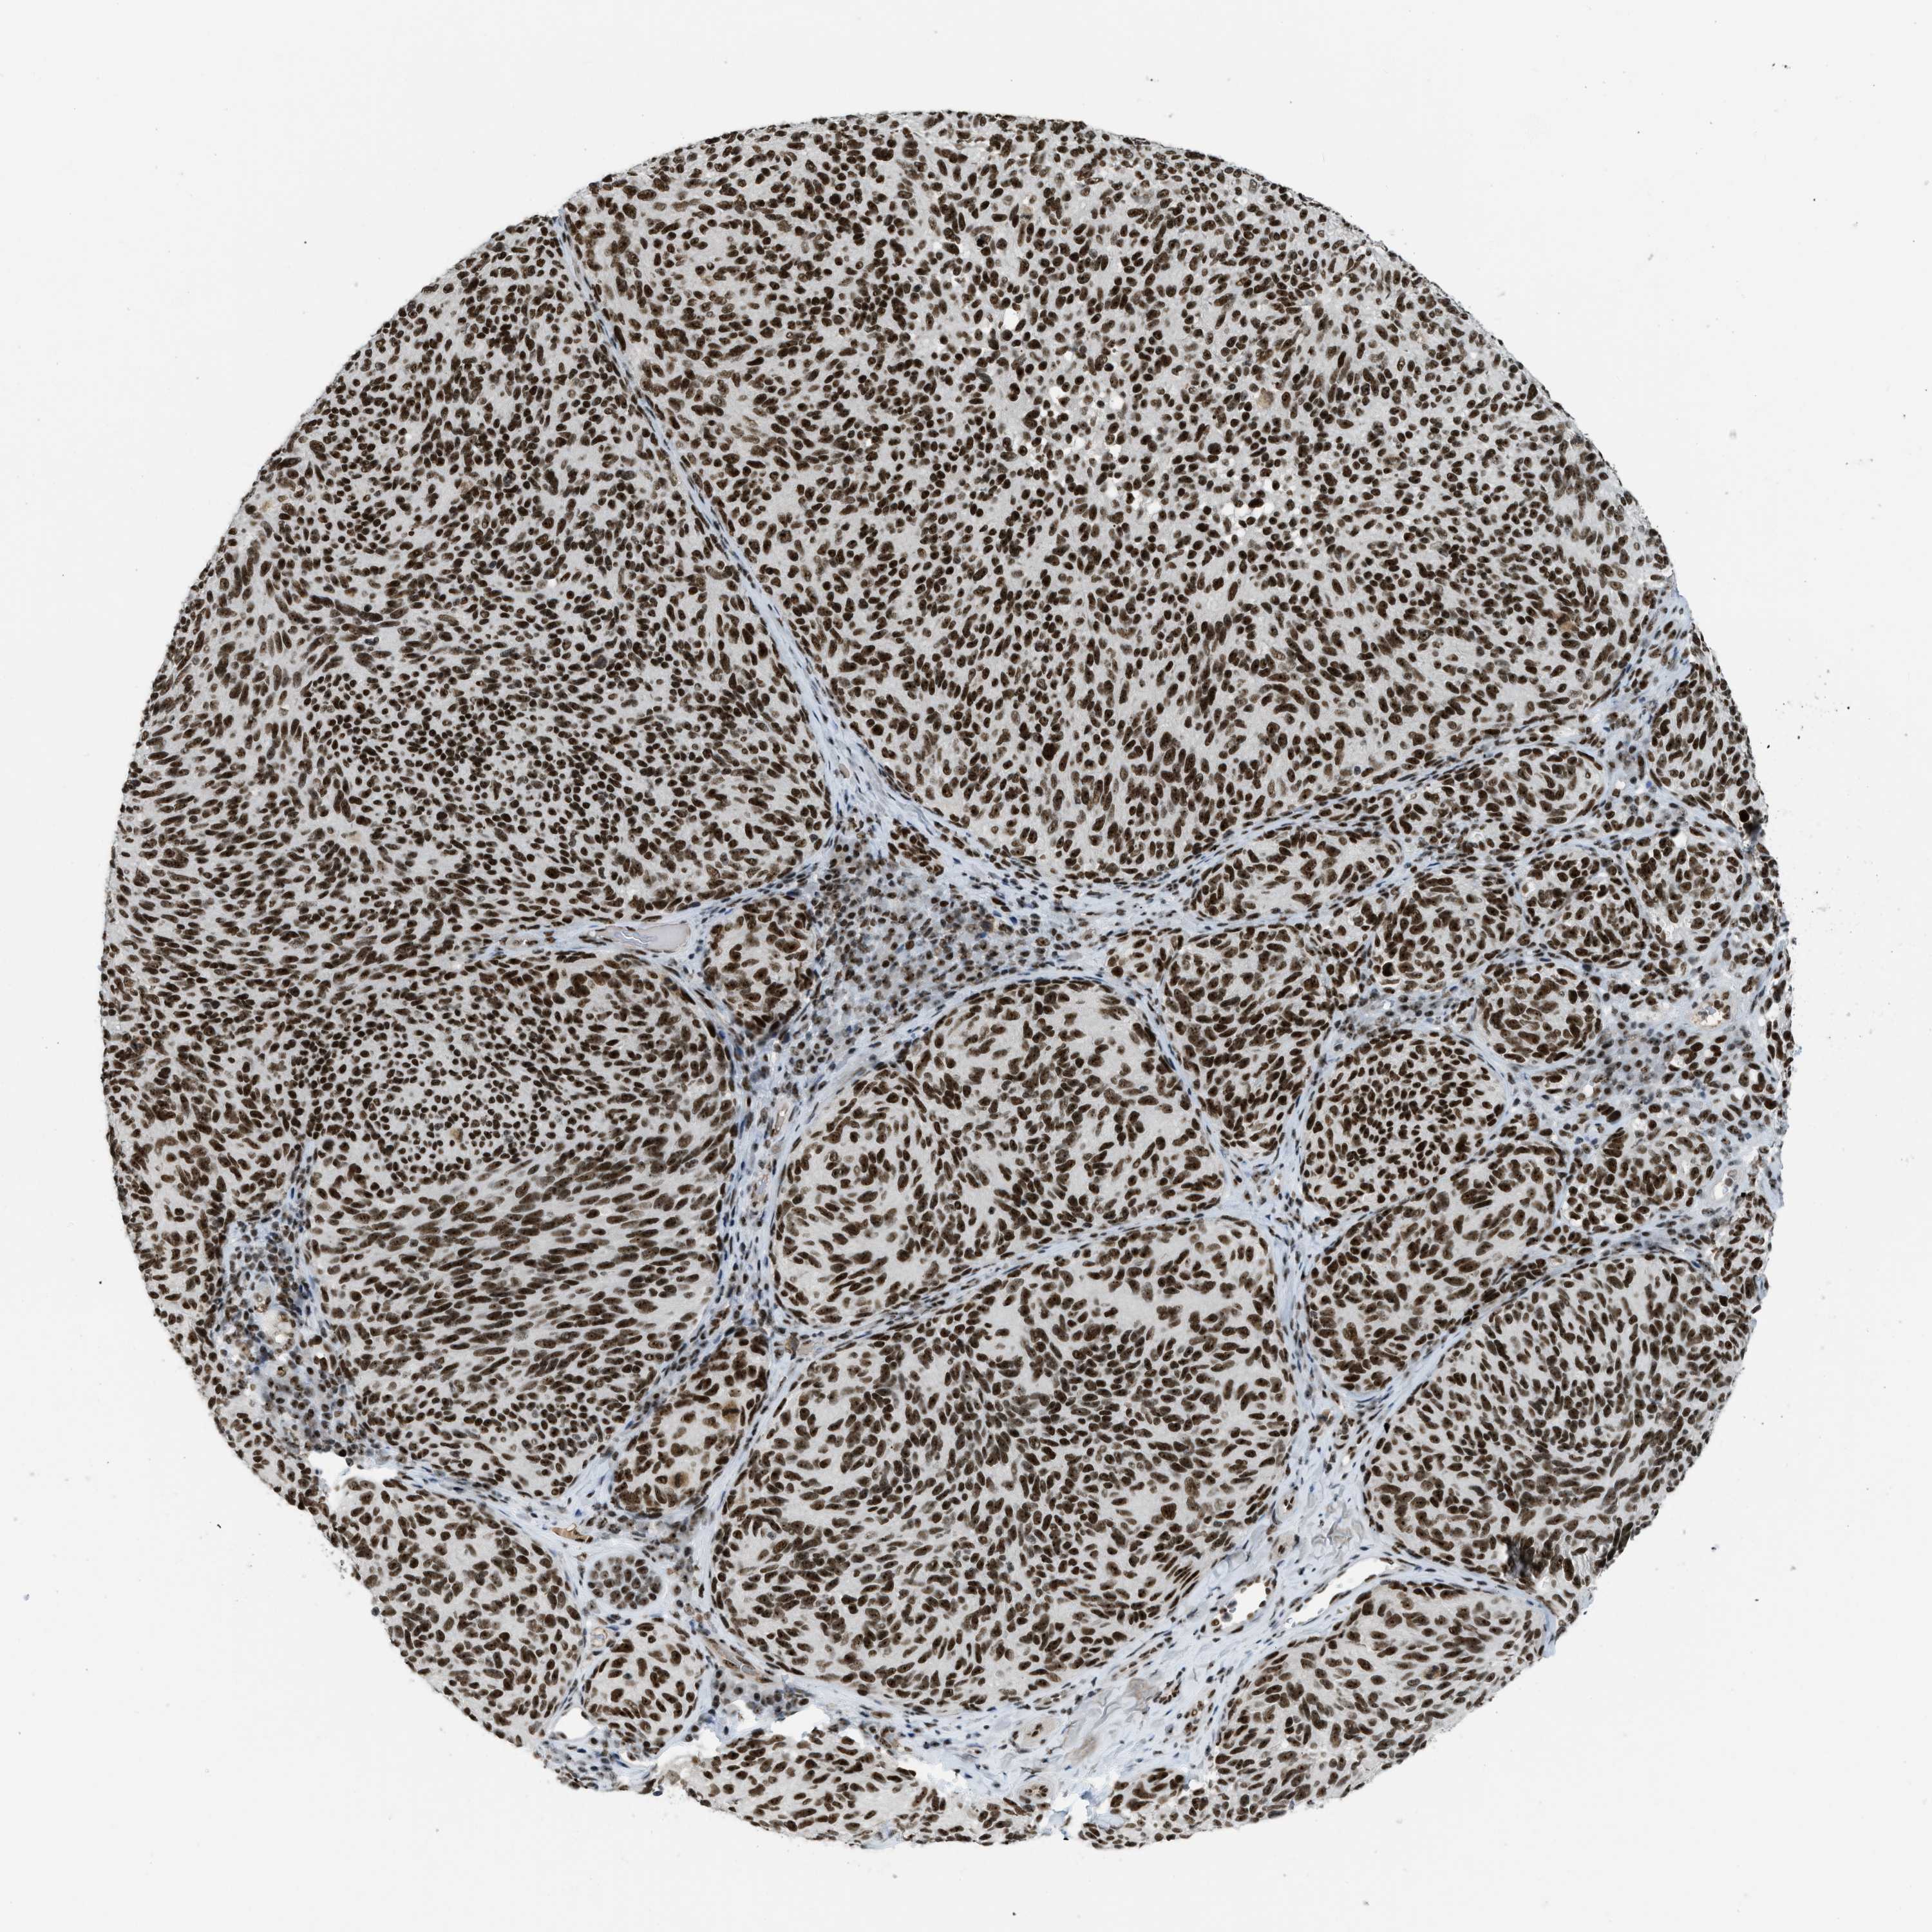

MELANOMA - Protein expressioni

A mouse-over function shows sample information and annotation data. Click on an image to view it in a full screen mode. Samples can be filtered based on level of antibody staining by selecting one or several of the following categories: high, medium, low and not detected. The assay and annotation is described here.

Note that samples used for immunohistochemistry by the Human Protein Atlas do not correspond to samples in the TCGA dataset.

Antibody stainingi

Antibody staining in the annotated cell types in the current human tissue is reported as not detected, low, medium, or high, based on conventional immunohistochemistry profiling in selected tissues. This score is based on the combination of the staining intensity and fraction of stained cells.

Each image is clickable and will lead to virtual microscopy that enables deeper exploration of all samples and also displays staining intensity scores, fraction scores and subcellular localization as well as patient and tissue information for each sample.

Antibody HPA018334

Staining

High

Medium

Low

Not detected

Intensity

Strong

Moderate

Weak

Negative

Quantity

>75%

75%-25%

<25%

None

Location

Nuclear

Cytoplasmic/membranous

Cytoplasmic/membranous,nuclear

Malignant melanoma, NOS

Malignant melanoma, Metastatic site